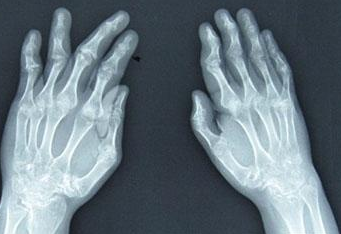

河南内风湿关节炎专科医院介绍到类风湿关节炎的症状是比较多样化的,多数患者是以手腕关节以及近端指间关节、掌指关节受累为主,出现受累关节的肿胀、压痛,活动受限,有的部分患者可以伴有发热、乏力、消瘦...[详细]